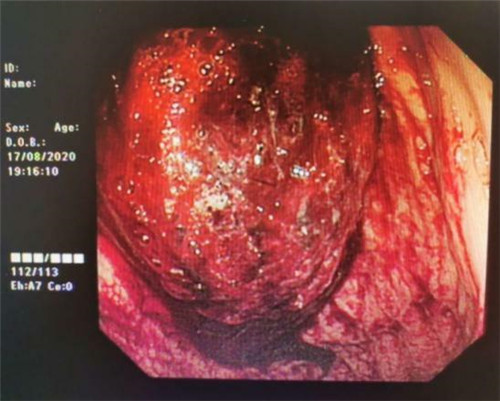

手术中,在镜下发现数条食管静脉曲张延伸至胃底,胃腔内有大量新鲜红色血液及血凝块,寻找到出血部位时仍在向外渗血,血压持续下降,患者时刻有生命危险。曹鹏副主任当机立断对曲张静脉破口处进行组织粘合剂及硬化剂注射,并对曲张静脉进行套扎治疗,在麻醉师陈琦的保驾护航下,整个过程不到半个小时,为患者成功止血,患者转危为安。